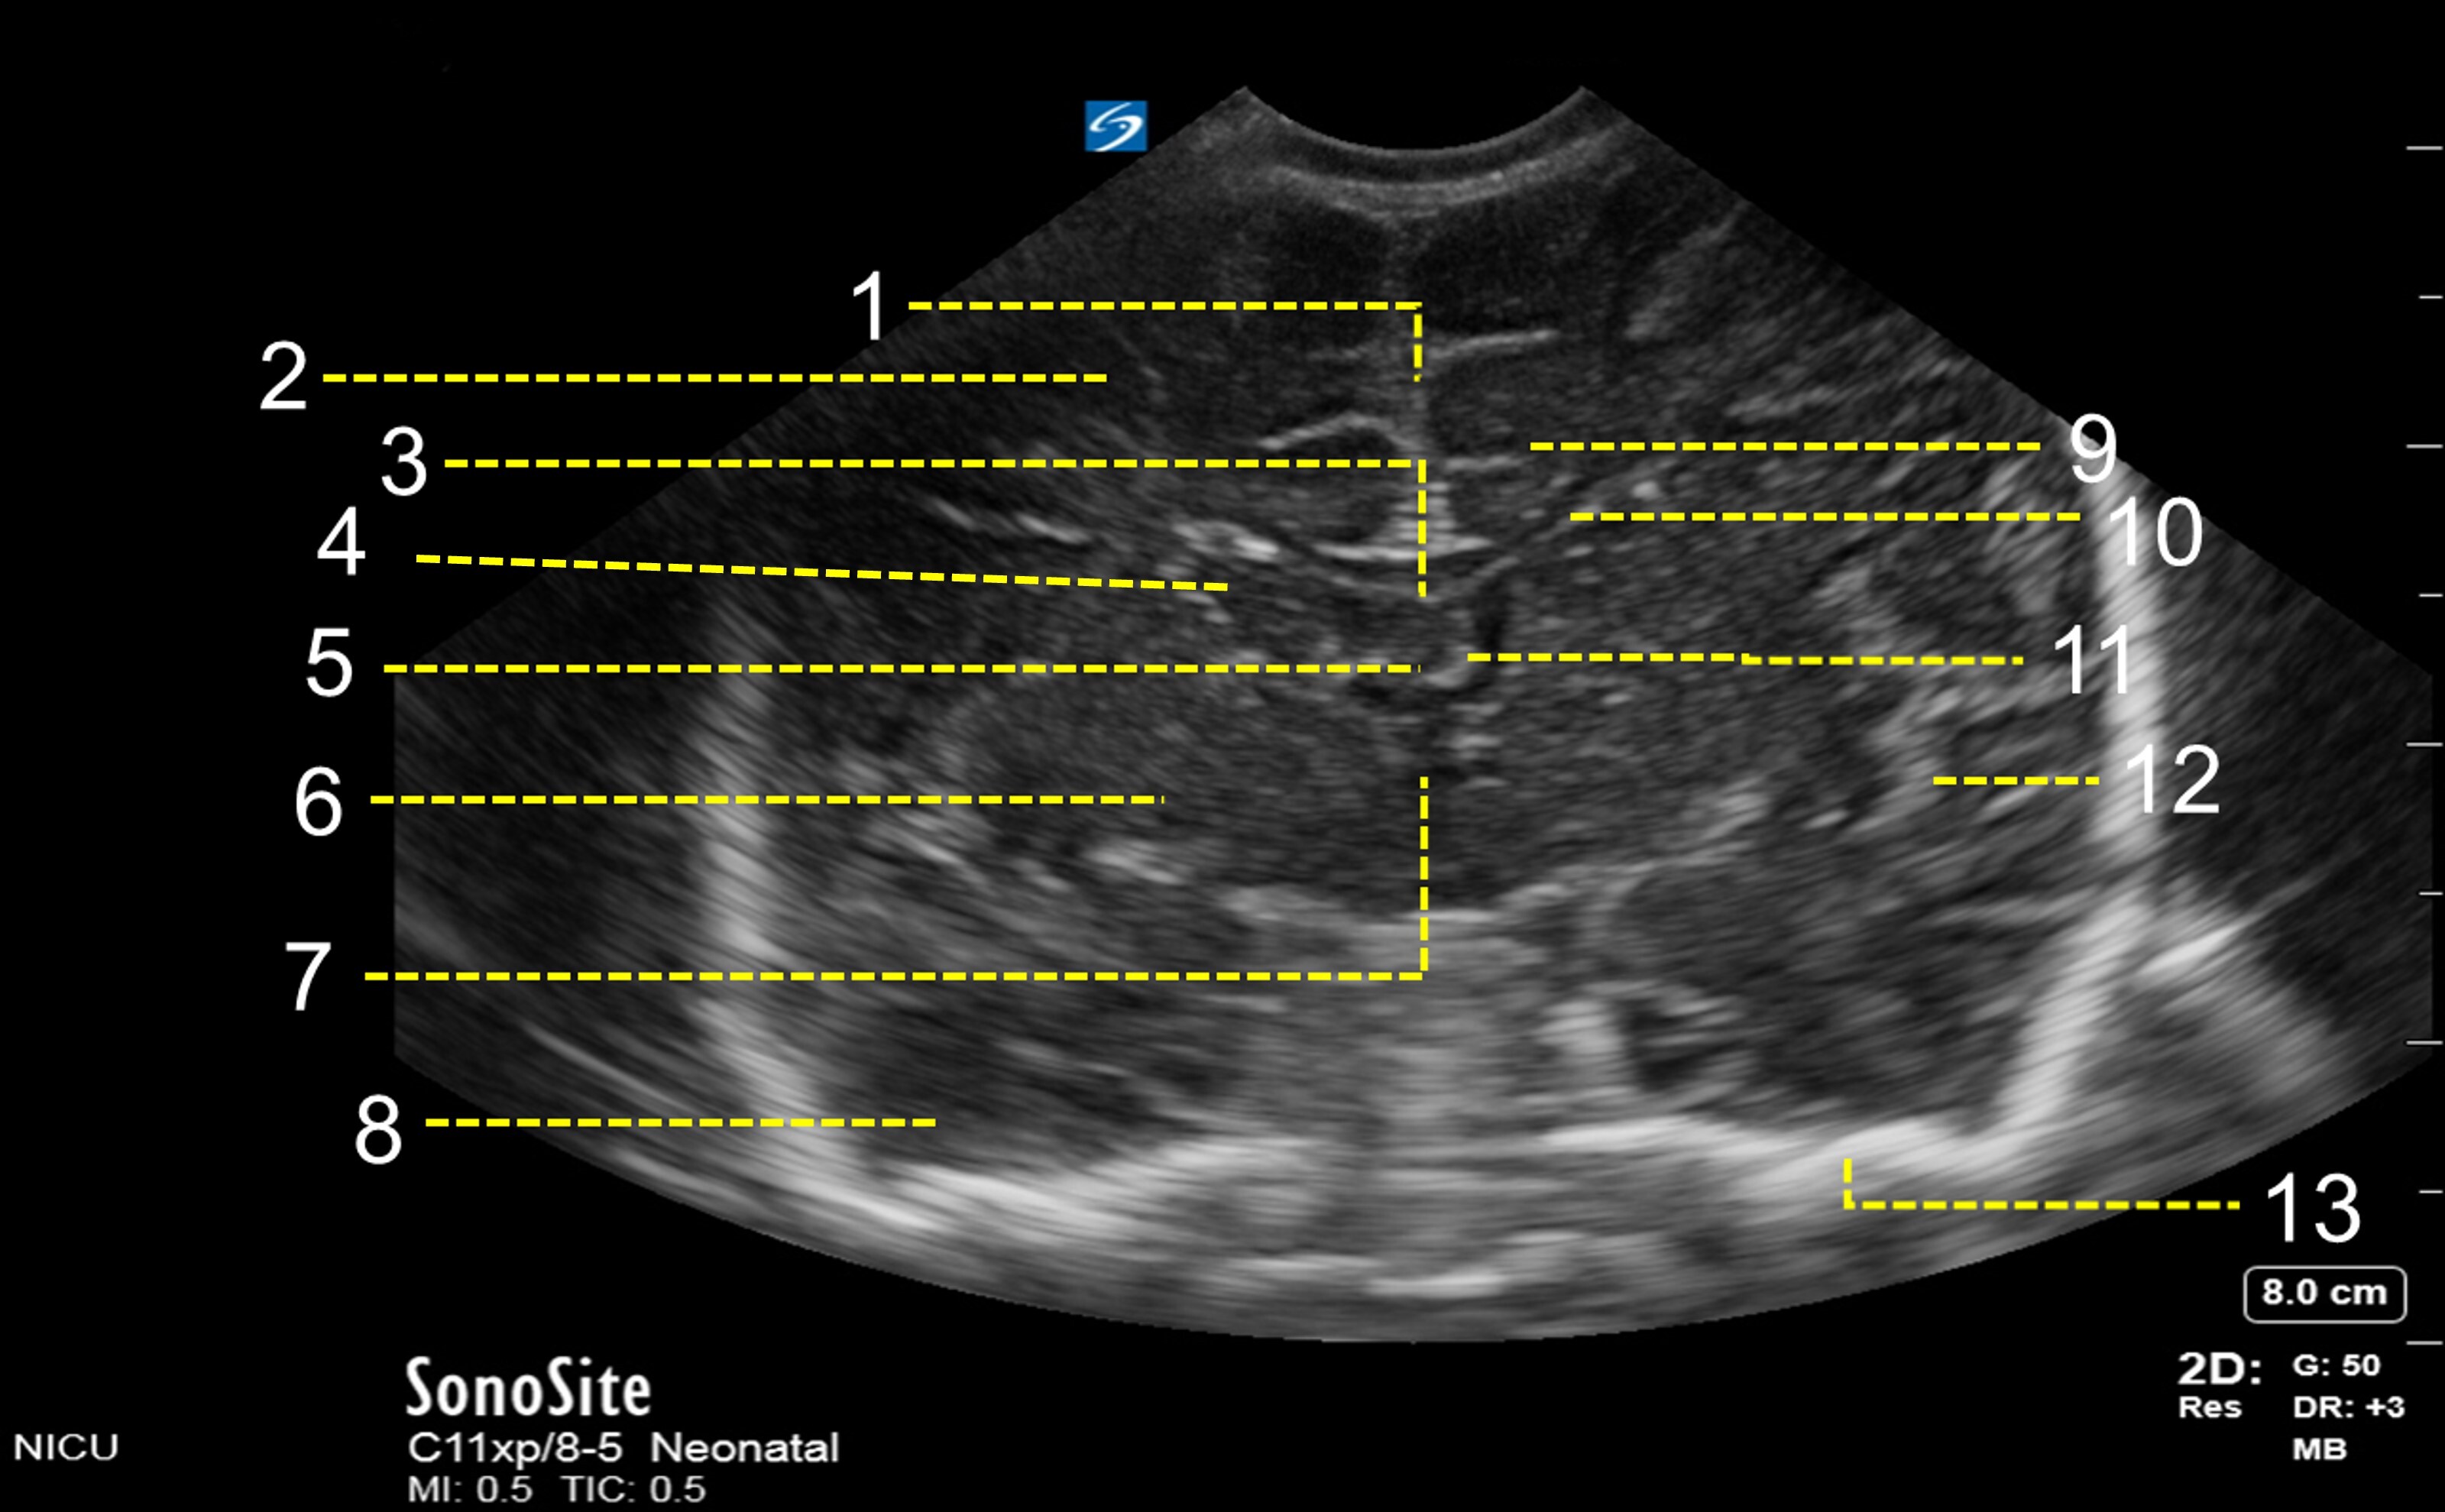

1. Interhemispheric Fissure

2. Frontal Lobe

3. Corpus Callosum

4. Caudate Nucleus

5. Cavum Septum Pellucidum

6. Basal Ganglia

7. 3rd Ventricle

8. Temporal Lobe

9. Cingulate Sulcus

10. Frontal Horn of Lateral Ventricle

11. Choroid Plexus in 3rd Ventricle

12. Sylvian Fissure

13. Skull